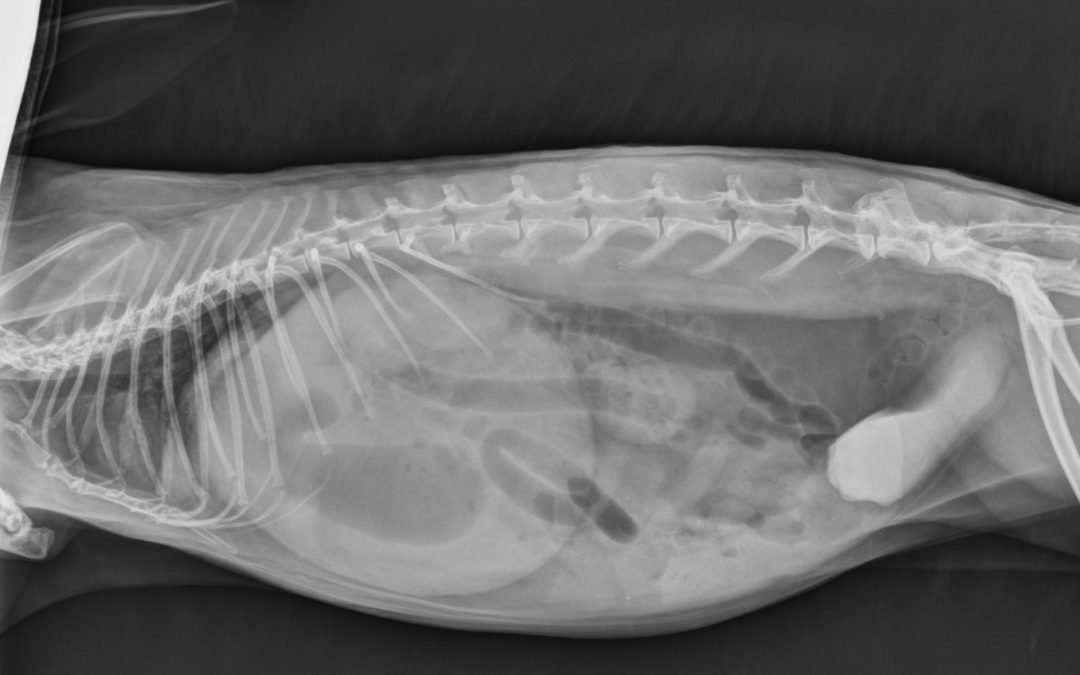

Hutches are still a permanent home for many pet rabbits, but they come from the old days of rabbit farming and the lab animal world. They are not a suitable home for rabbits. They can cause a myriad of health problems, one of which is bladder sludging. Rabbits absorb...